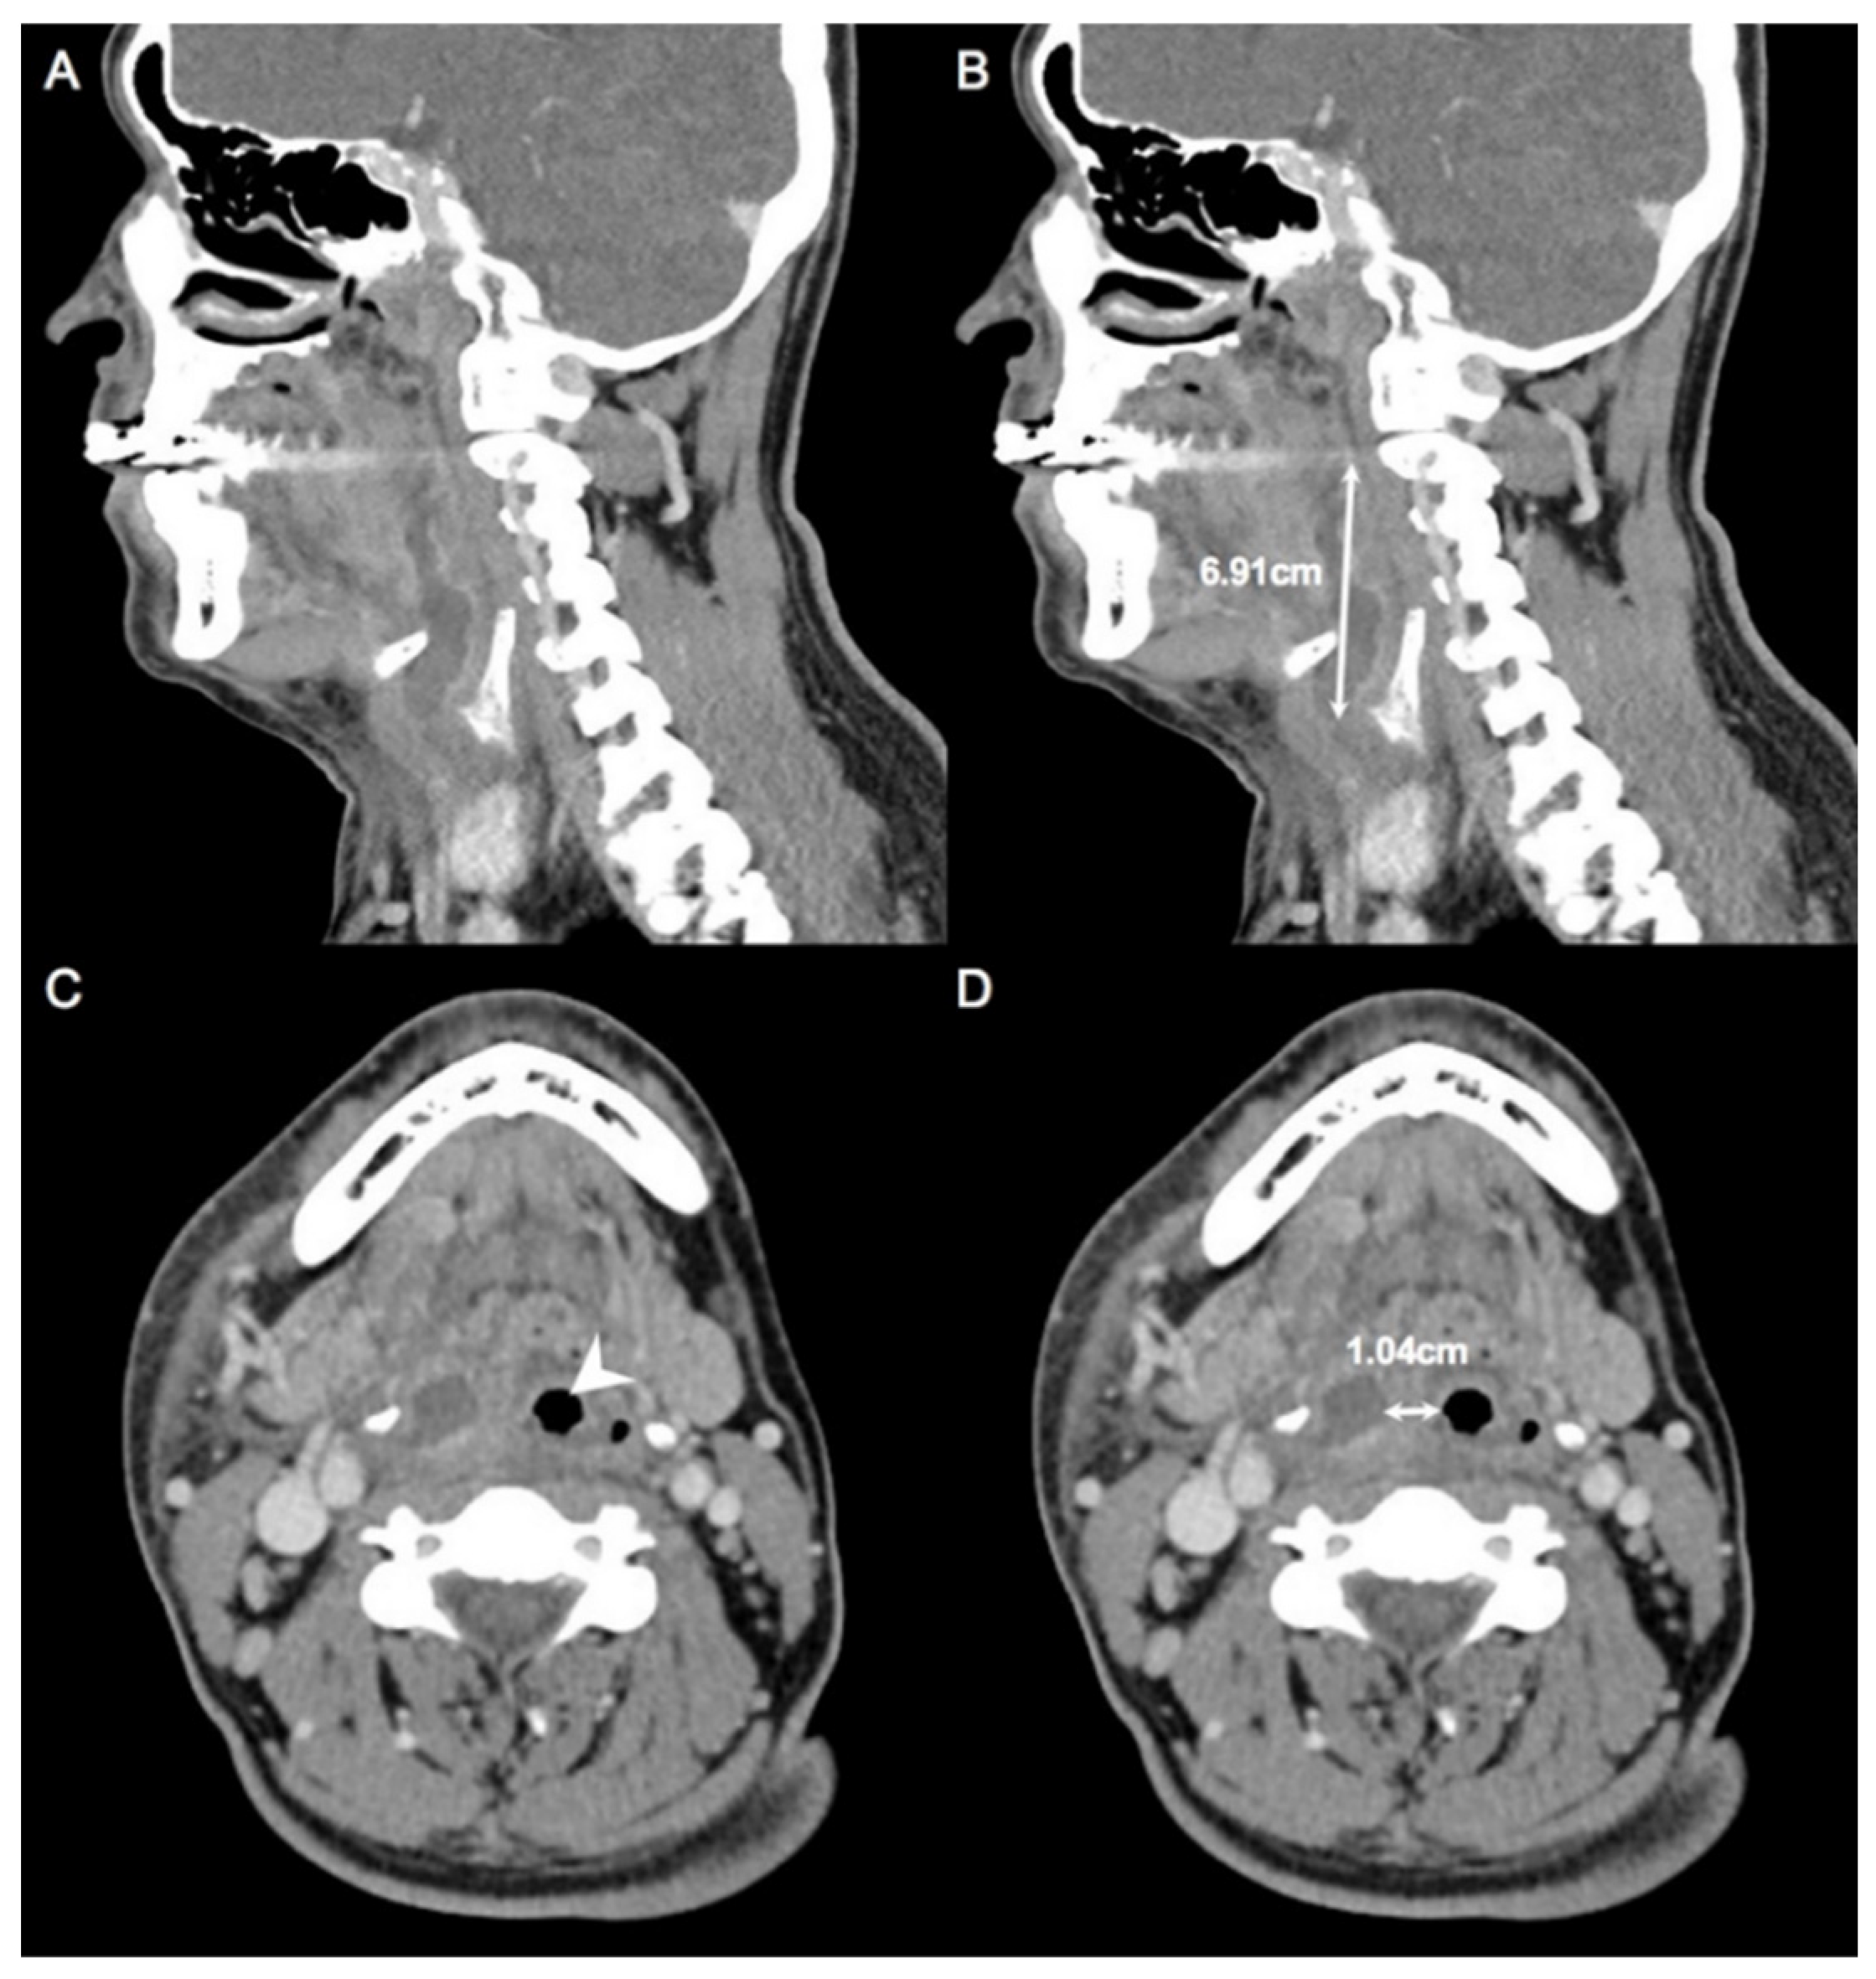

| Maximum diameter of abscess, cm ± SD | 6.36 ± 3.08 |

| Nearest distance from abscess to inlet of trachea, cm ± SD | 1.41 ± 1.35 |